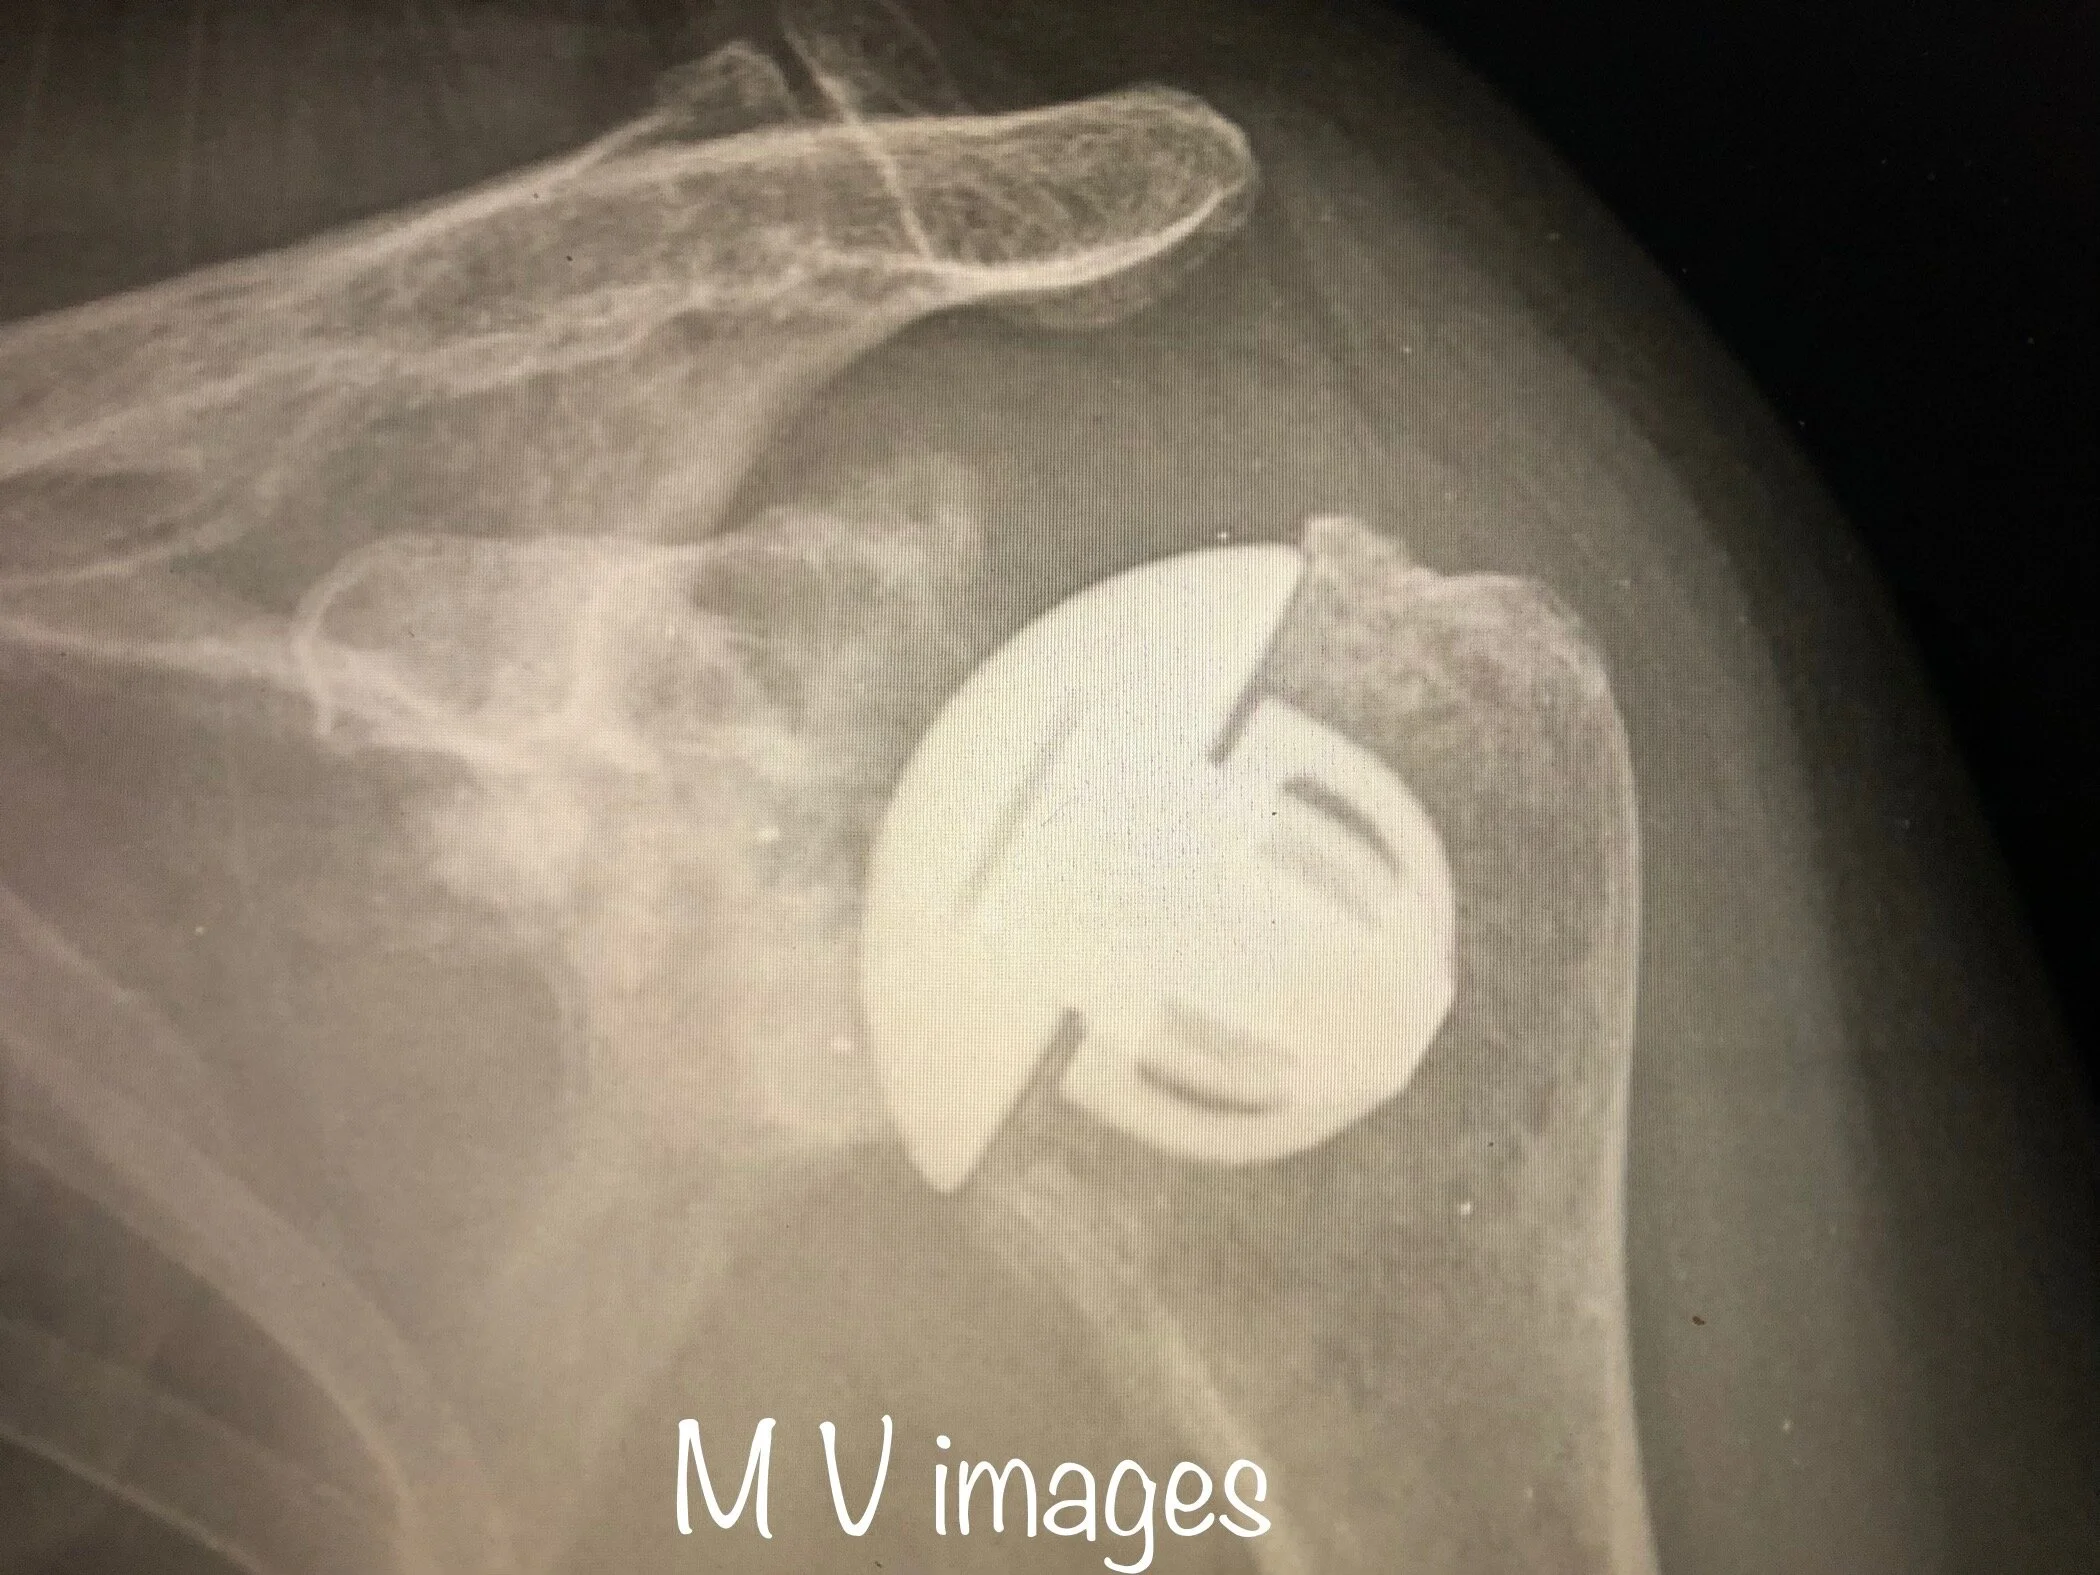

IMG_9587.jpg

The above image is a X-ray of a shoulder with advanced shoulder arthritis with osteophytes. The patient had severe shoulder pain with poor quality of life and required joint replacement.

After joint replacement

The image above is a shoulder X-ray following a total shoulder joint replacement, where the ‘ball (humeral head) and socket (glenoid)’ are replaced.

Mathew uses the Mathys Medical shoulder replacement system.